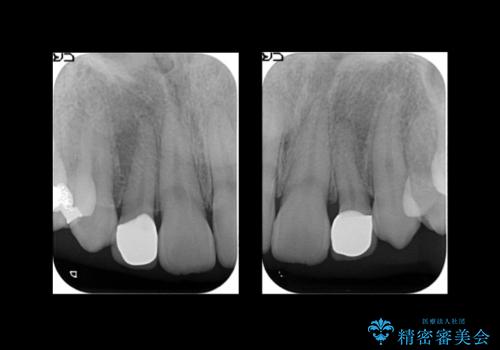

抜歯したスペースを使い、歯並びを整え、さらにその隙間を利用して細い歯を大きく整えてセラミックで被せるという総合的な治療を行いました。

マウスピース矯正→上顎両側2番のセラミック、左下67の虫歯治療 の順で行いました。

- 137万円 内訳:矯正治療95万円 セラミック治療42万円 (前歯2本28万円(ジルコニアクラウン・スペシャル) 左下奥歯2本15万円(emaxインレー、ヴェレッツァクラウン))ホワイトニング(エクセレント)3万円費用は治療当時の料金となります